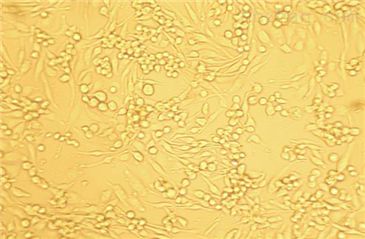

SK-N-BE(2)

- 生长状态:

贴壁生长

SK-N-BE(2)(人神经母细胞)复苏

1. 把冻存管从液氮中取出来,立即投入37℃水浴锅中,轻微摇动。液体都融化后(大概1-1.5分钟),拿出来喷点酒精放到超净工作台里。

2. 把上述细胞悬液吸到装10ml培养基的15ml的离心管中(用培养基把冻存管洗一遍,把粘在壁上的细胞都洗下来),1000转离心5分钟。

3. 把上清液倒掉,加1ml培养基把细胞悬浮起来。吸到装有10ml培养基的10cm培养皿中前后左右轻轻摇动,使培养皿中的细胞均匀分布。

4. 标细胞种类和日期、培养人名字等,放到CO2培养箱中培养,细胞贴壁后换培养基。

5. 3天换一次培养基。